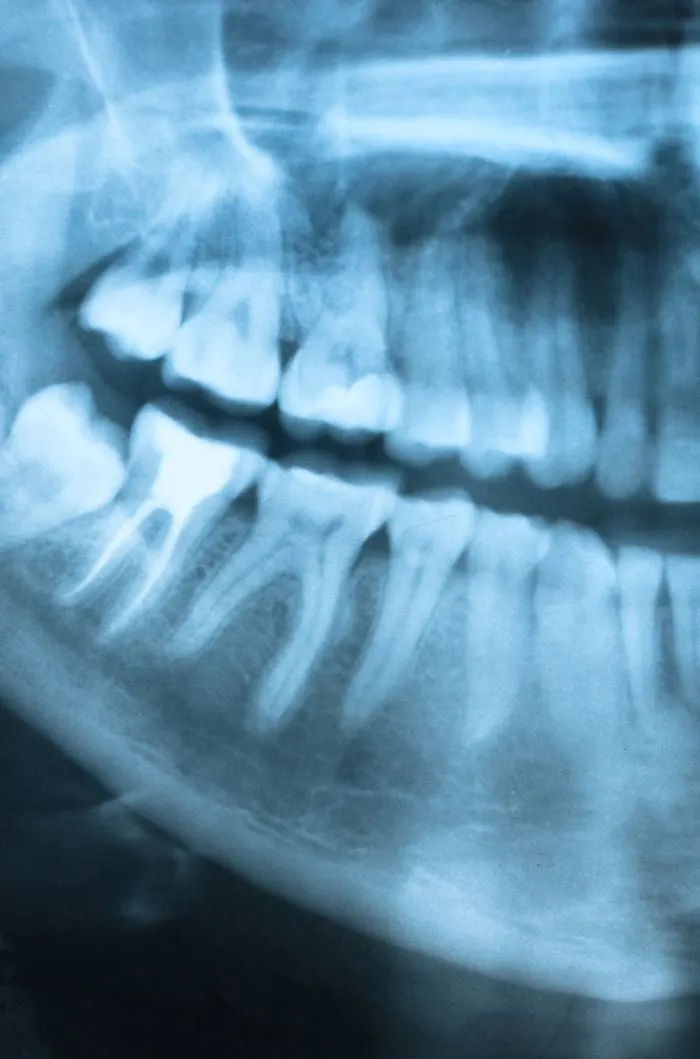

When you arrive, our first goal is to understand what hurts and why. We will ask questions about your symptoms, when they started, and what makes them better or worse. We may take digital X-rays and do a gentle exam to find the exact problem.